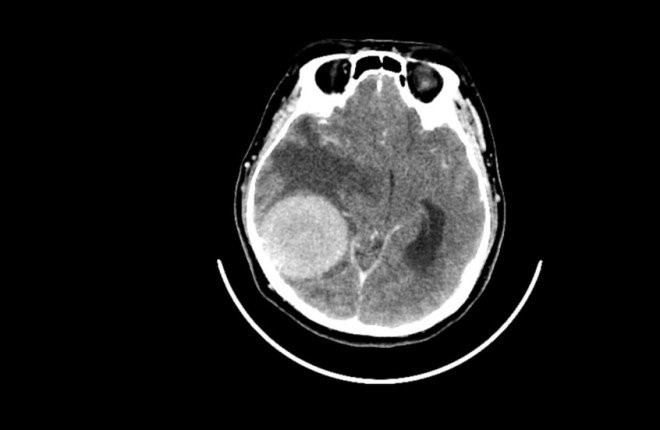

دراسة صادمة تكشف.. القلق والدوار قد يكونان إنذارًا مبكرًا لأورام الدماغ!

في اكتشاف طبي لافت، كشفت دراسة حديثة أن القلق النفسي والدوخة لا يرتبطان فقط بالأورام الدماغية الحميدة كأعراض جانبية، بل قد يلعبان دورًا مباشرًا في تفاقمها.

الدراسة، التي أجراها باحثون من جامعة واشنطن، ركزت على الورم الشفاني الدهليزي أو ما يُعرف بـ ورم العصب السمعي، وهو ورم حميد يصيب العصب المسؤول عن السمع والتوازن وينمو ببطء.